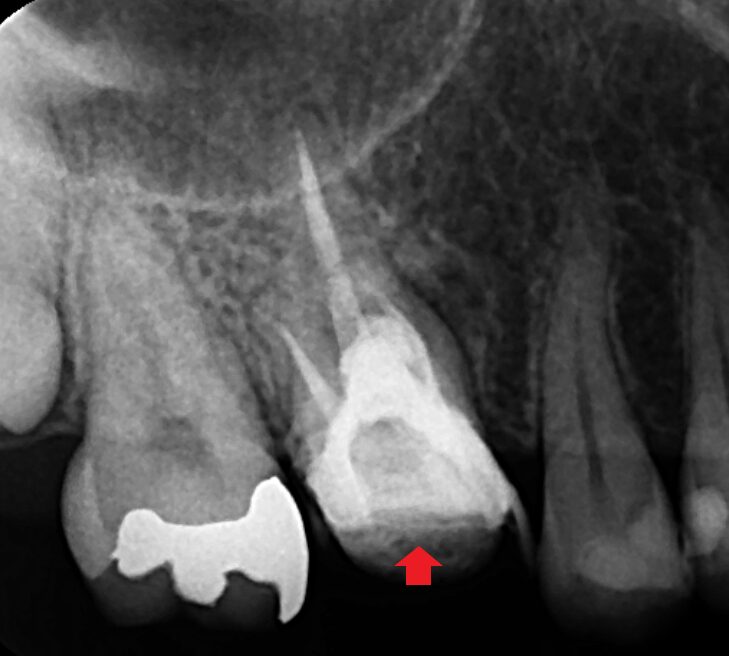

精密再根管治療で膿の改善をはかりました。分岐部穿孔部のパーフォレーションリペアと根管充填を行った時のレントゲン画像です。